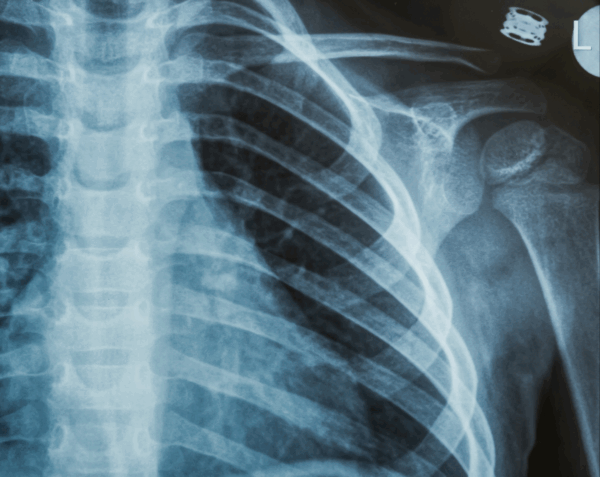

A left rib series X-ray provides a detailed set of images focused on the left side of your rib cage. Physicians use this test to detect fractures, dislocations, bone abnormalities, or complications affecting the lungs and chest wall. At Desert Mobile Medical, we deliver this vital diagnostic service directly to you with mobile X-ray technology, ensuring comfort, privacy, and fast results—without the hassle of traveling to a hospital or urgent care.

A rib series typically includes multiple images at different angles, giving physicians a comprehensive view of the rib structure and surrounding chest area.